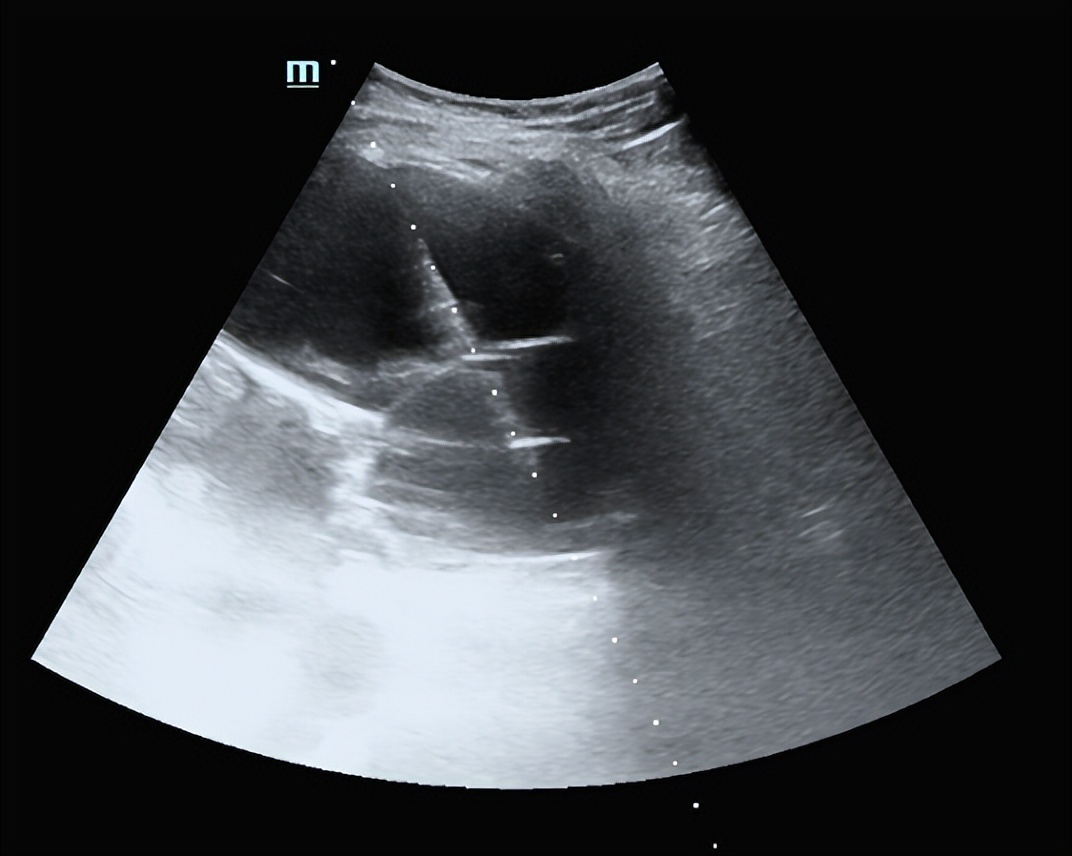

超声:肝内多发囊肿

介入超声治疗方案:对最大的囊肿进行超声引导下经皮穿刺置管引流,对其他直径<8cm的囊肿分别进行穿刺抽液、硬化治疗。

按照大小排序,对第2、3号囊肿进行常规穿刺硬化治疗,采用18G PTC针穿刺,抽吸出囊液95ml、75ml,生理盐水冲洗囊腔,40ml、30ml无水乙醇硬化囊腔10分钟抽出,囊腔内保留无水乙醇3ml。

重叠囊肿连环穿刺